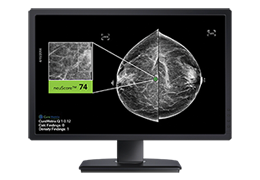

成像智能。

Eclipse 成像智能功能提供强大的处理能力和最佳质量的影像,同时减少质量错误并提高剂量效率。

凭借 AI、专有算法和先进的影像处理能力,提供出色的影像质量和无与伦比的诊断信心。